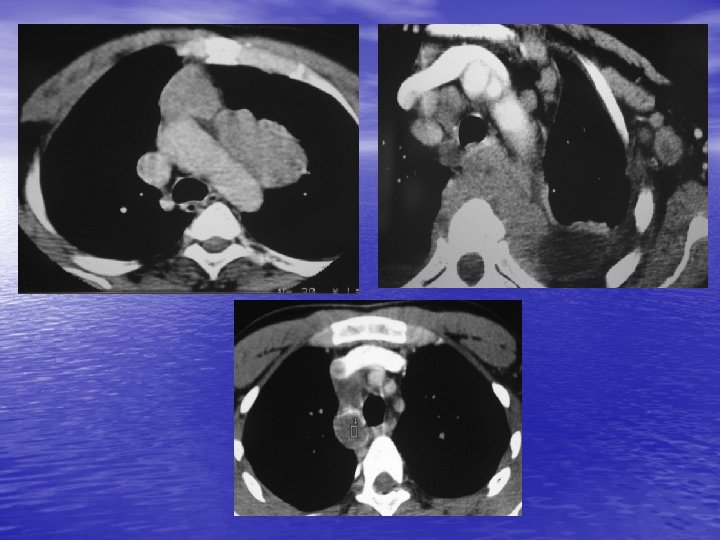

6. ADENOPATHIES MEDIASTINALES - Etiologie n° 1 des masses du médiastin. - Bénigne ou maligne. - Sarcoïdose : caractère symétrique. - Lymphome malin (Hodgkin, LMNH : caractère asymétrique). - Métastases : ++ cancer bronchique. - Surtout médiastin moyen.